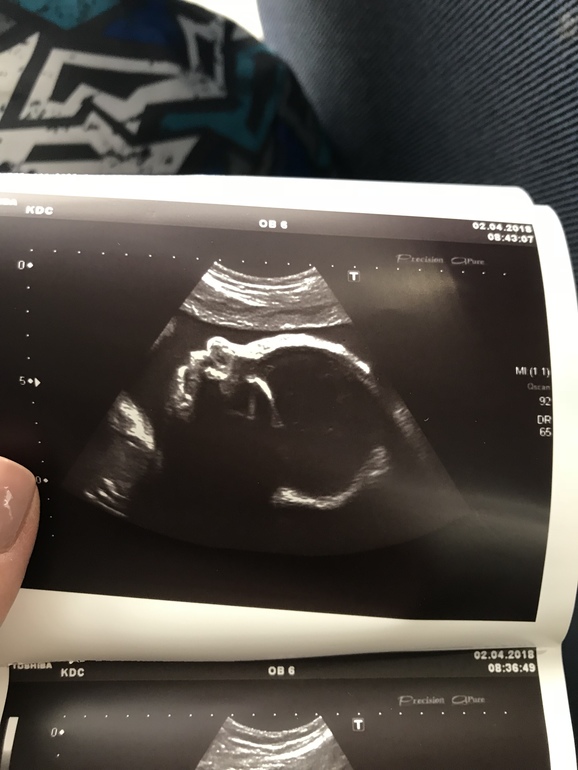

Загоняюсь или что-то не так с нижней челюстью?

Страхи, переживания и немножечко нытьяУзист ничего не сказал, а я только на фото увидела, прям режет глаз мне эта челюсть. У старших детей посмотрела: красивый профиль с нормальным подбородком. А тут не пойму ракурс такой, и рот открыт может..может у кого были такие картинки? :)

Тоже такой загон был,а потому что на узи у него был открыт рот,так и засняли и я прям переживала,что какой-то разрез рта большой,на втором скрине было и зд,все отлично со ртом))вот это фото) и он на всём видео такой,видимо глотал воды)

єто просто на такой длине волны фотка сделана))) Узи оно же как мрт , типа как слоями быстро картинку передает. Вот сейчас видно щечку, датчик приближает и уже визуализируется челюсть, по такому принципу и видно же и внутренние органы и внутренности внутренних органов)))

На фото глотал, да еще и слой кожи уже миновали, видны именно уже кости черепа